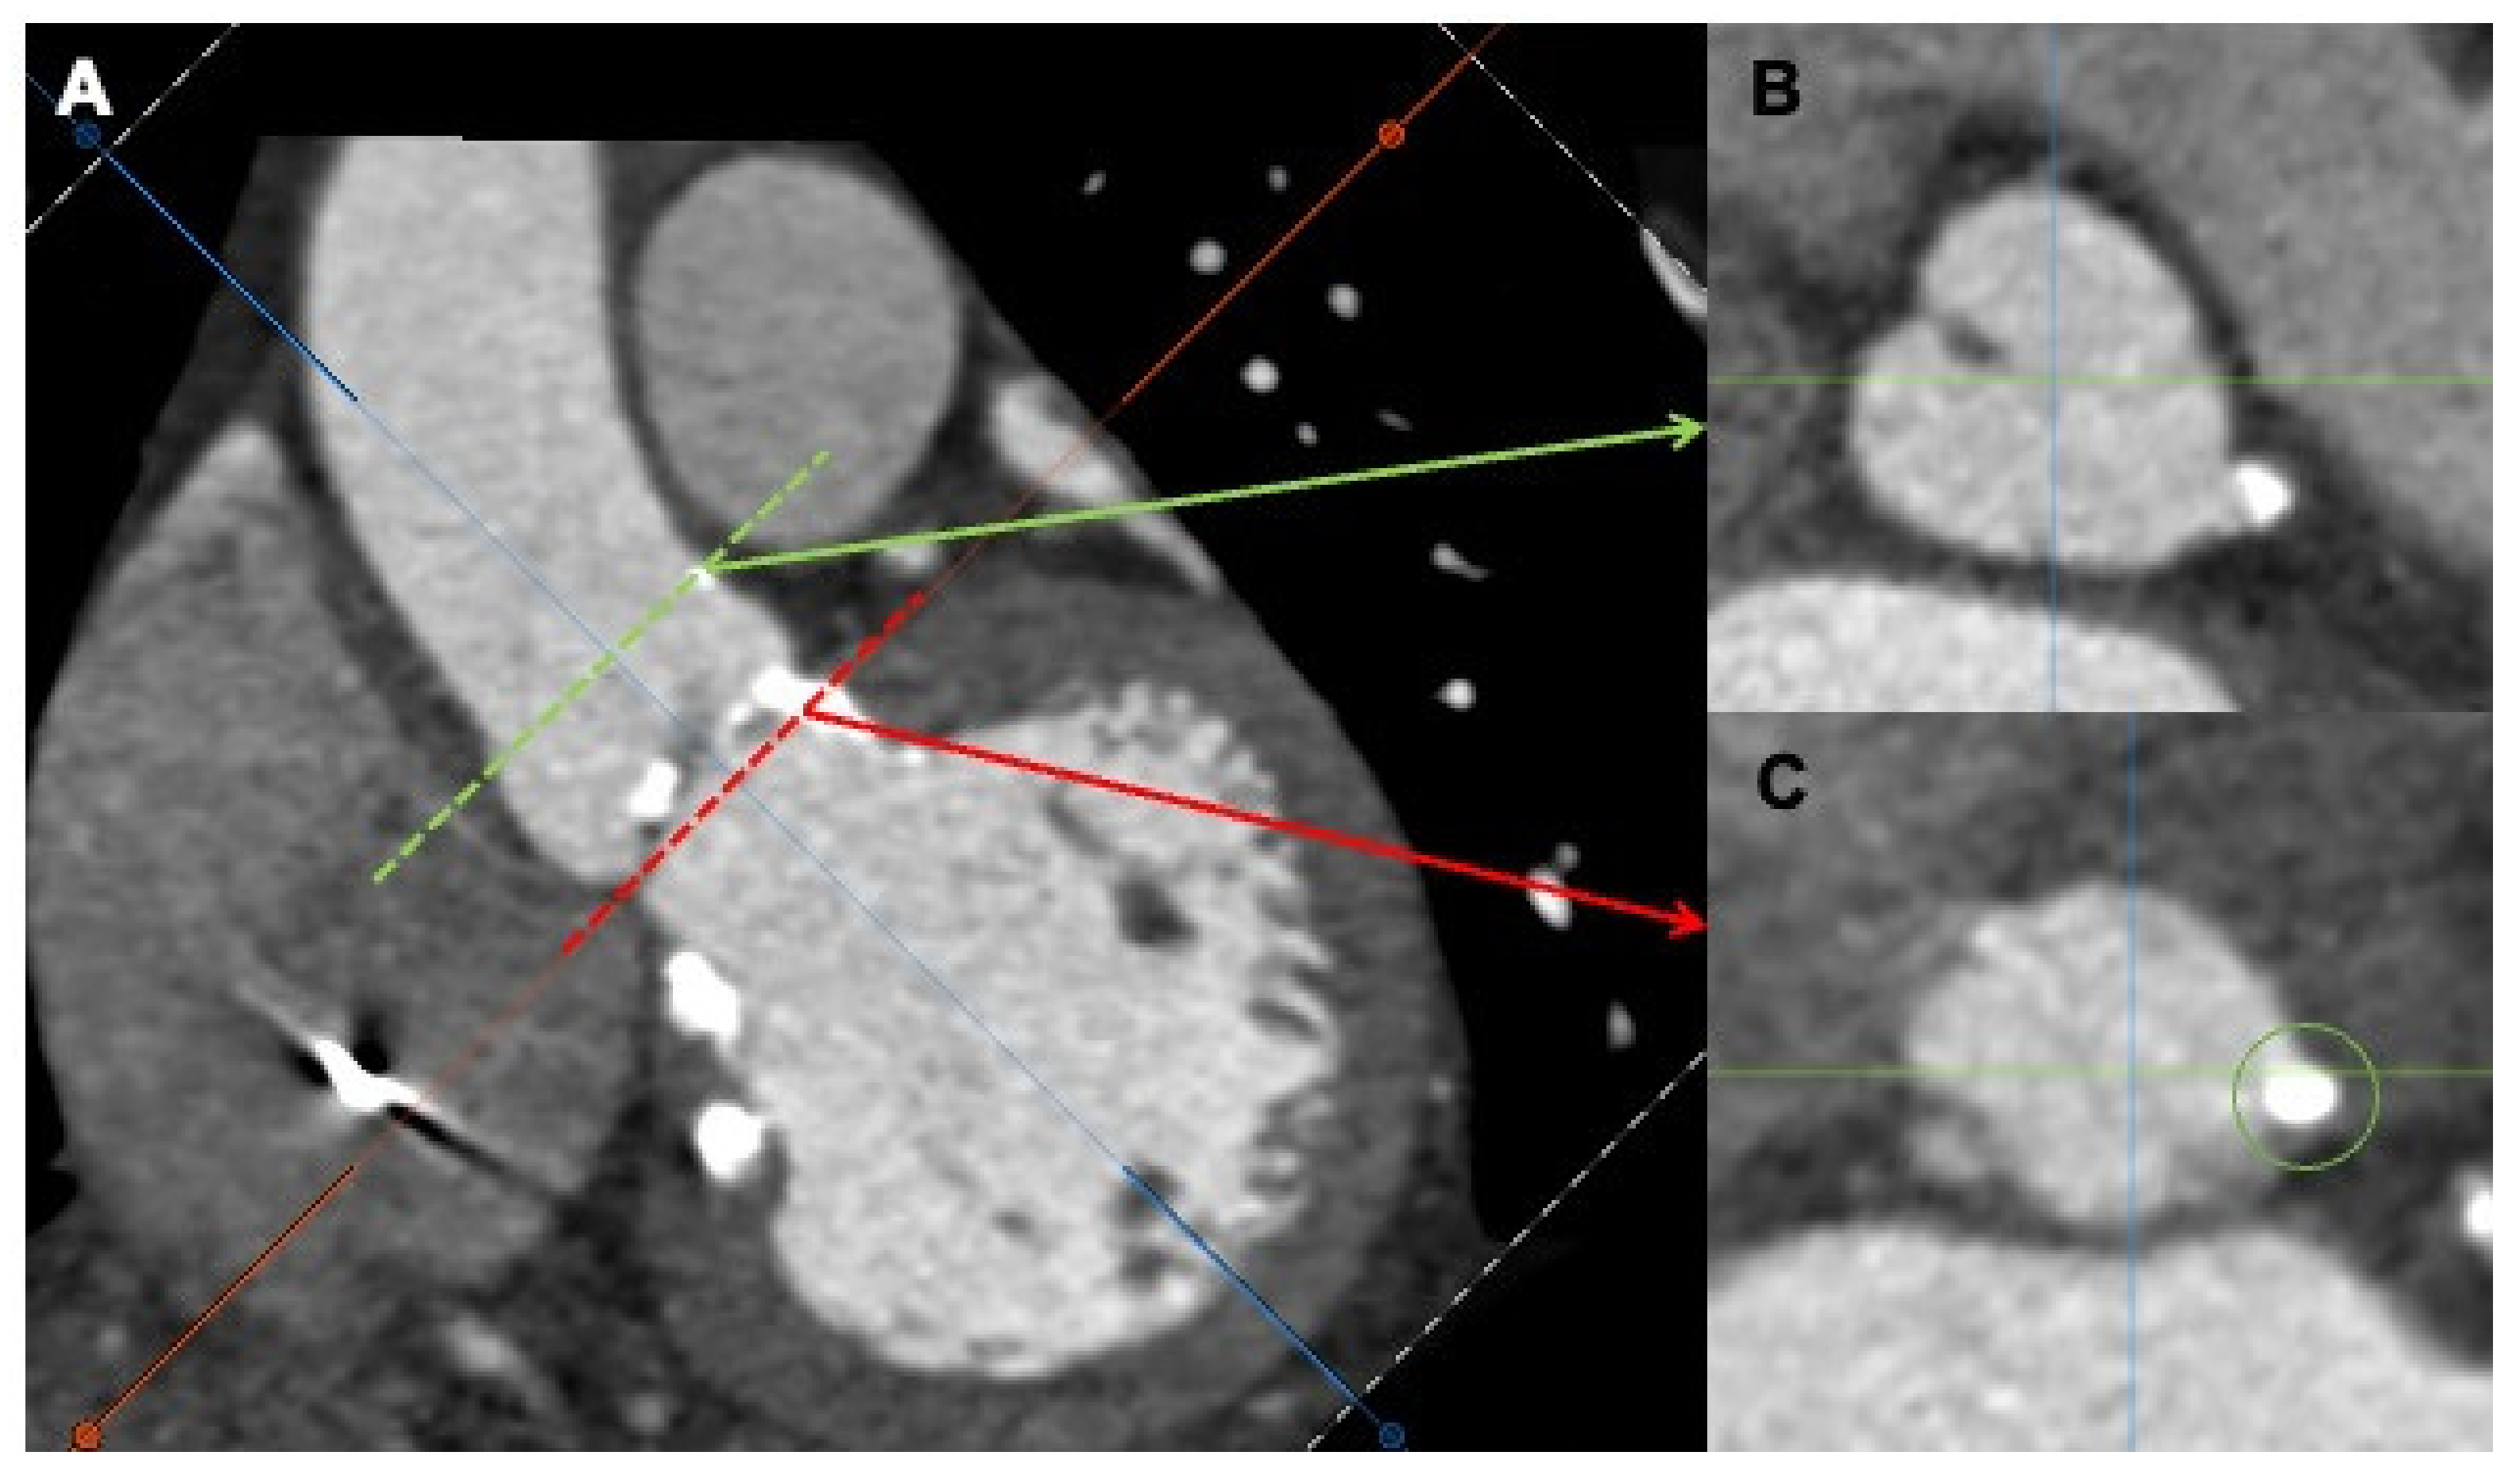

Figure 4.

Multidetector computed tomography angiography (MDCTA) showing severe calcification at the level of the left coronary cusp (A). Transversal views at the left coronary artery (B), green arrow and the aortic ring (C), red arrow.

In particular, the device-landing-zone calcium volume is associated with PVLR, particularly after SE valves, and the risk increases by 8% every 100 mm3 of calcium volume [19] (Figure 6).